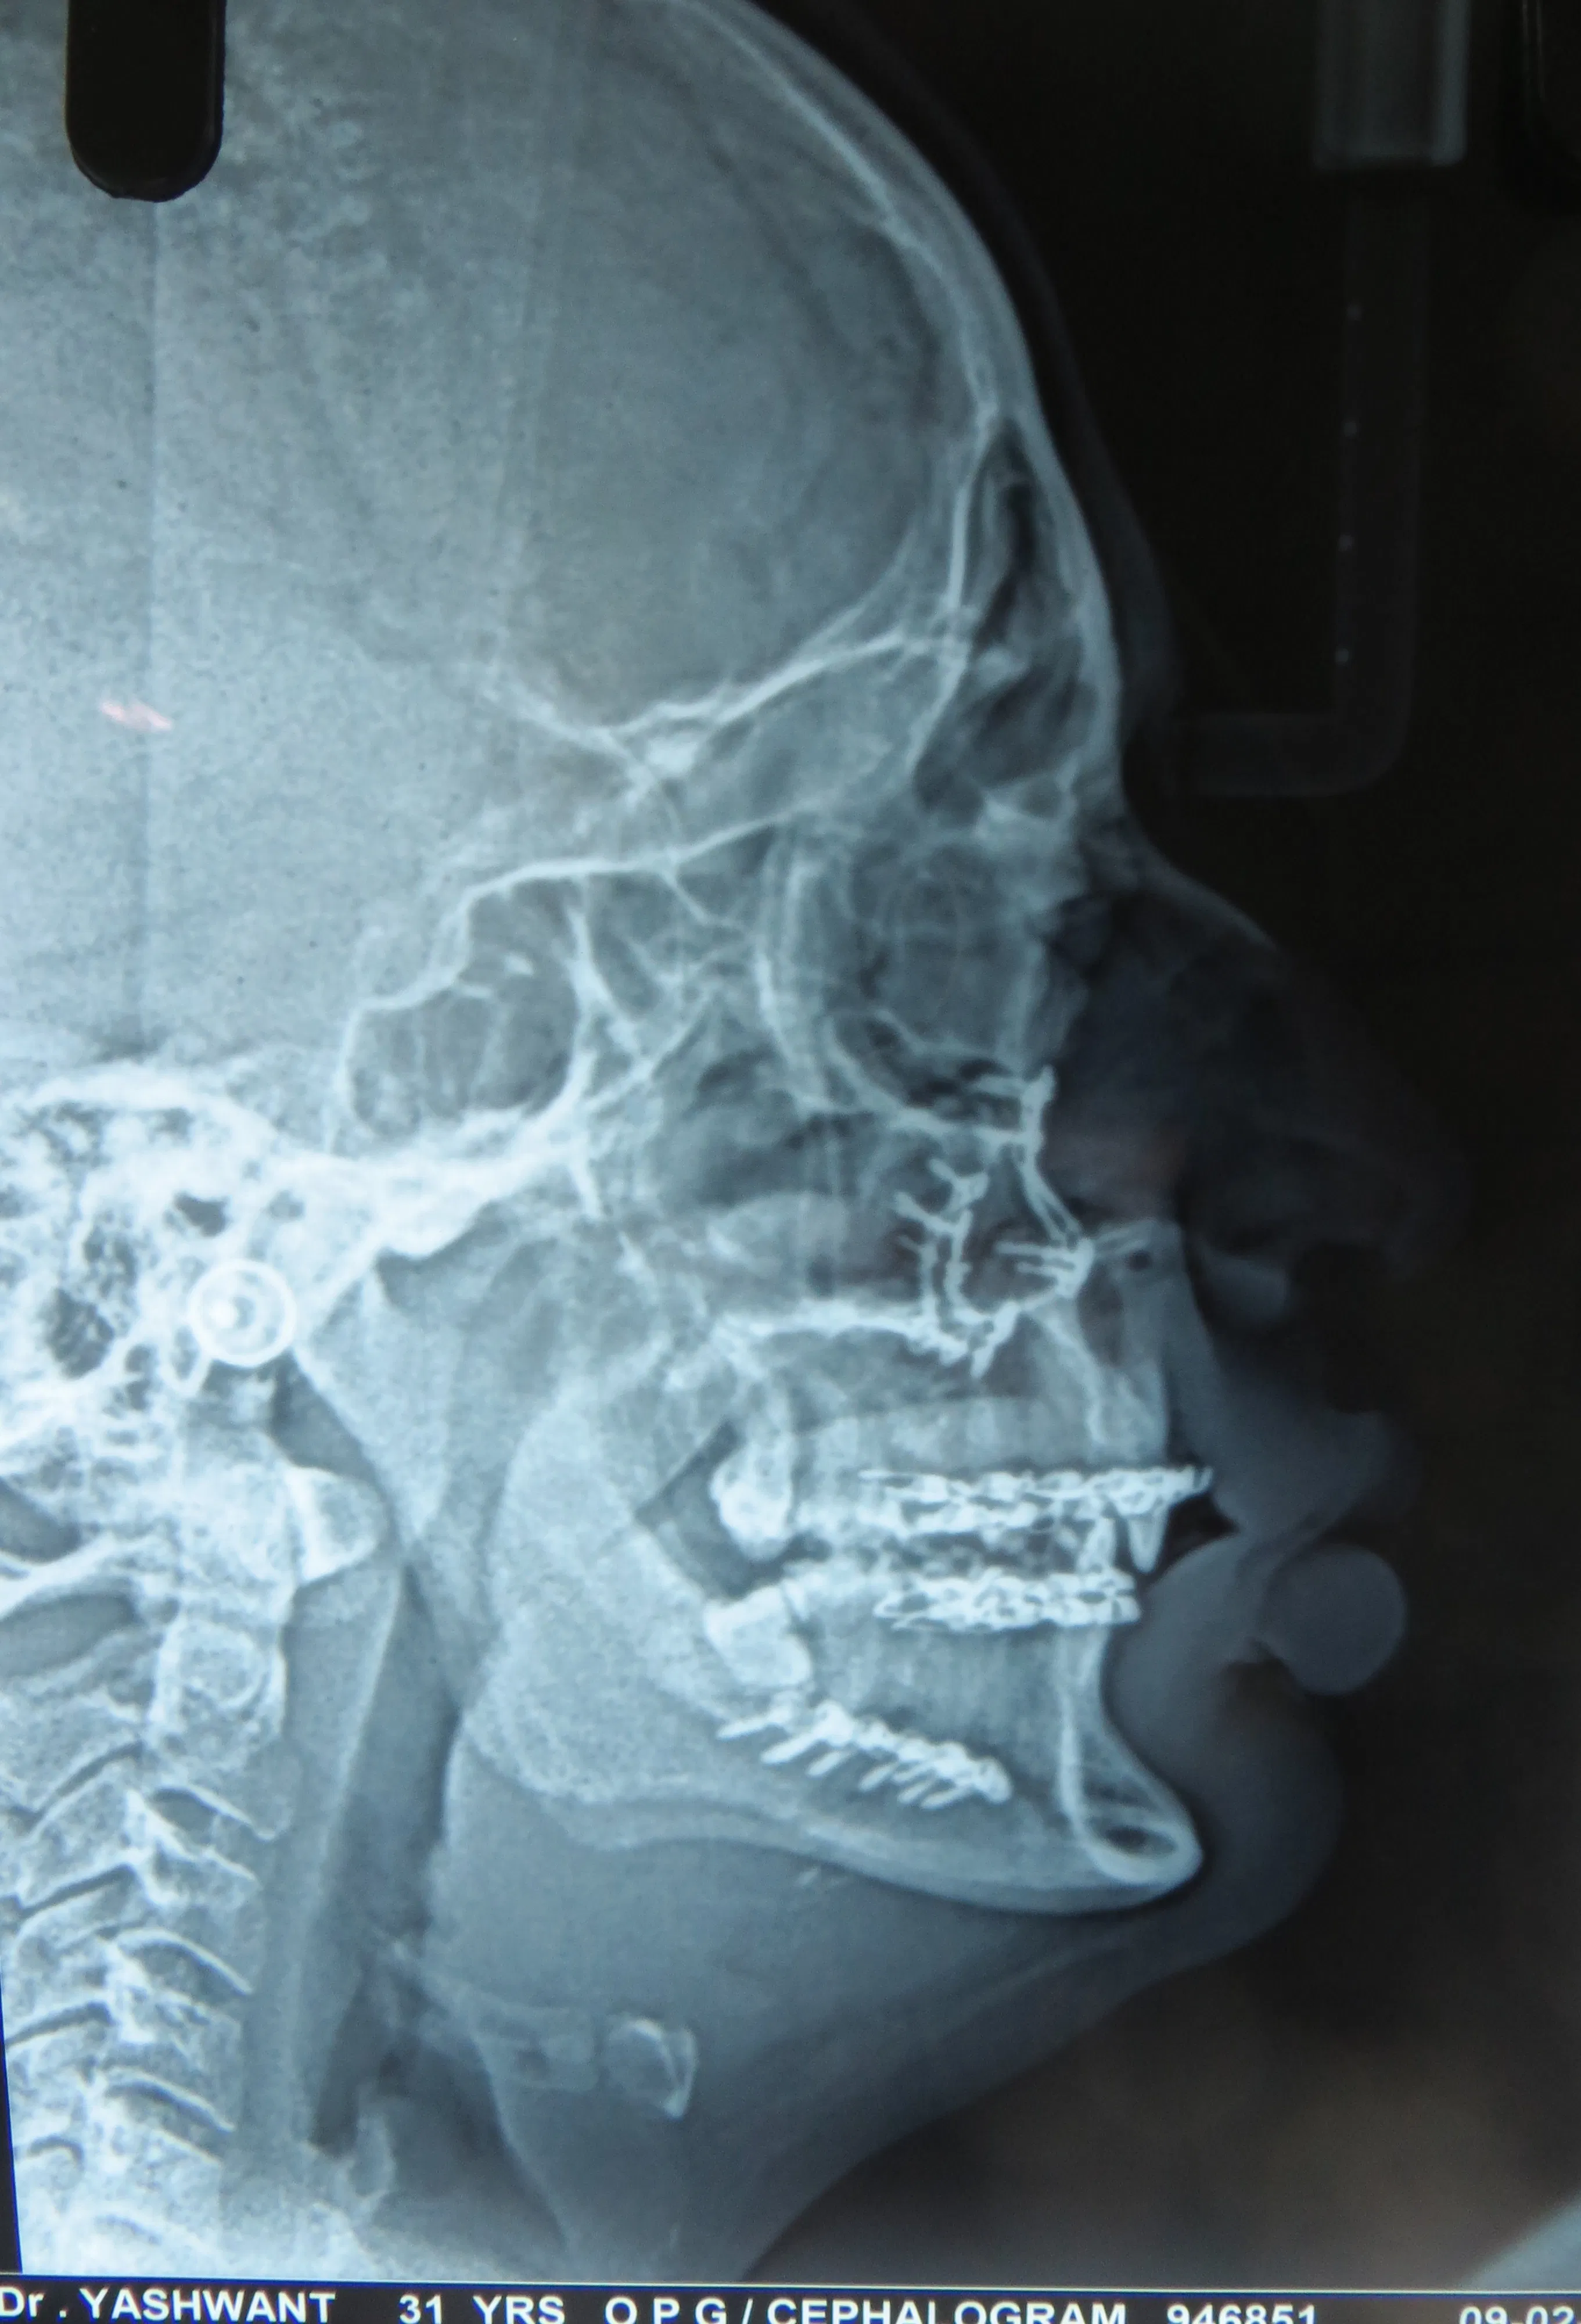

ORTHOGNATHIC AND COSMETIC SURGERY

Do you feel your jaws are not in alignment? Are your jaws very prominent or very retrusive? Do you want your chin to be more prominent? All these problems can be addressed with a proper assessment, xrays and corrective surgery. Improve your confidence and self esteem with cosmetic orthognathic surgery.